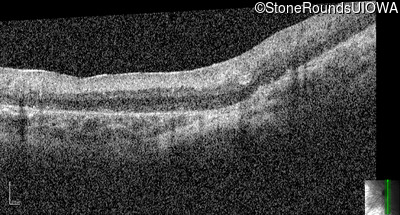

Optical Coherence Tomography - Right -

No Light Perception

Optical Coherence Tomography - Left -